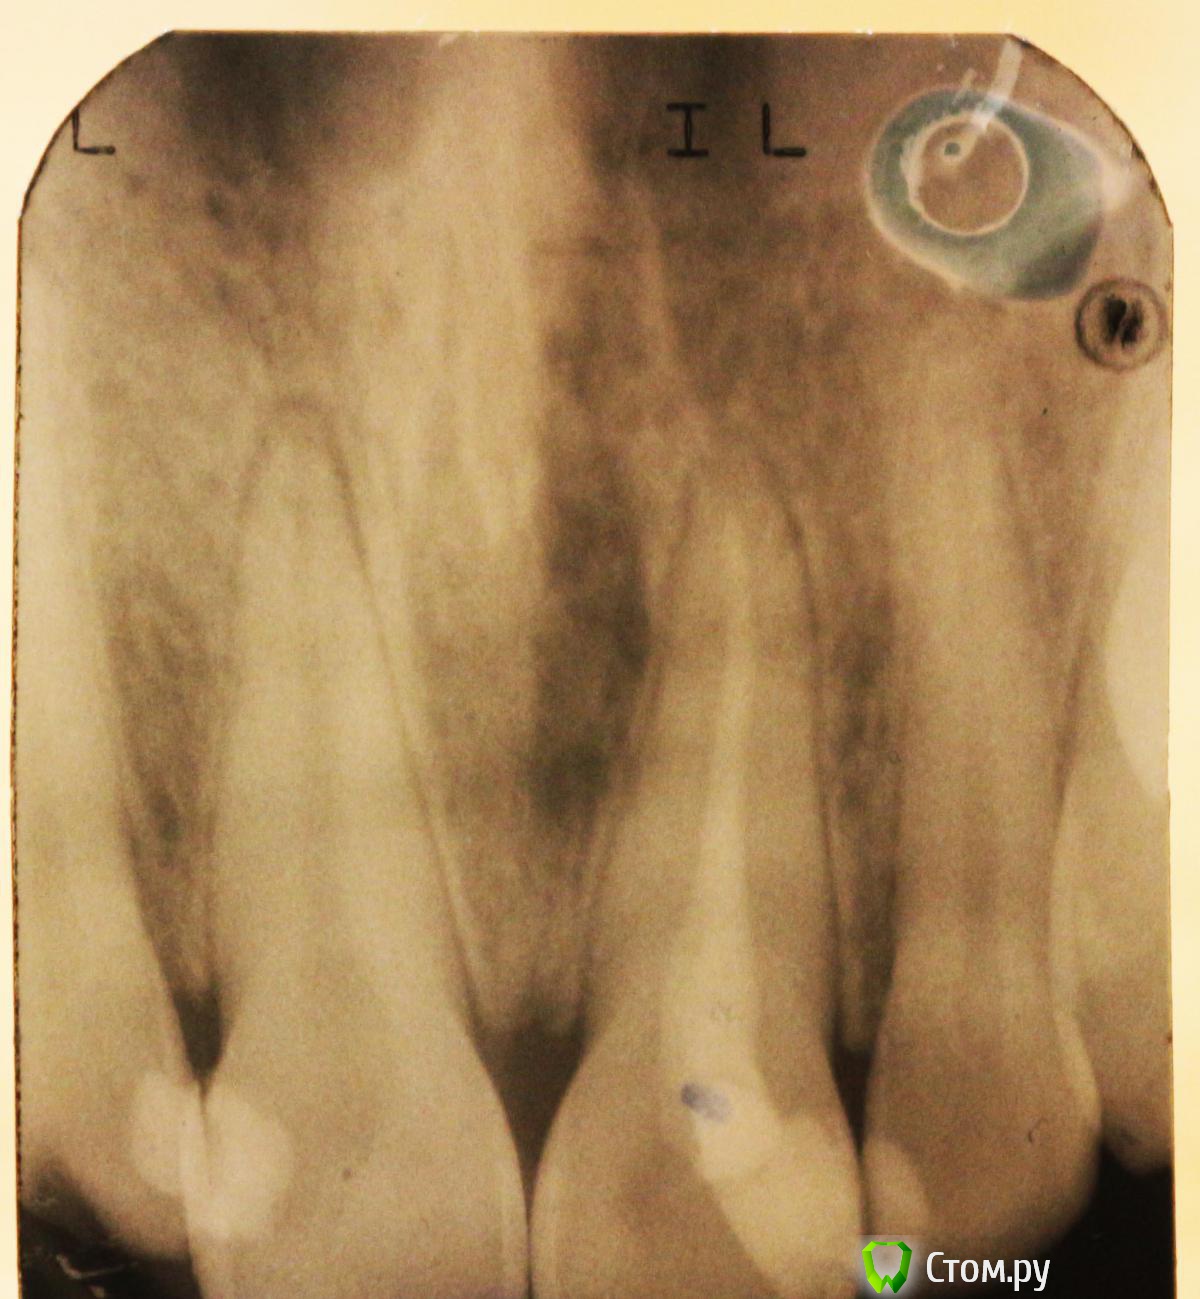

bmr Опубликовано 19 января, 2014 Поделиться Опубликовано 19 января, 2014 Здравствуйте. Такая проблема. Пролечили зуб. Врач поставил диагноз - пульпит. Прошел месяц после лечения. Первые 10 дней зуб болел сильно. Потом боль начала стихать. Теперь она еле заметная. Возникает при нажатии на зуб пальцем с внешней стороны. При накусывании боли как таковой нет. Сделали гентген. Врач сказал, что вывел гуттаперчу, чтобы не образовалась киста. Сказал, что перелечивать не нужно, само пройдет. Сказал, что требуется полоскать водой с содой. Проверье, пожалуйста, правильные ли выводы сделал врач. Не хочется терять передний зуб.До леченияПосле Ссылка на комментарий

bmr Опубликовано 20 января, 2014 Автор Поделиться Опубликовано 20 января, 2014 Почему? Не знаю, видно ли это на фото, но на снимке отчетливо видно потемнение вокруг выведенной гуттаперчи. Врач сказал, что это гнойный мешочек и он рассосется сам. Организм справится. Возможно ли это? Ссылка на комментарий

anvladd Опубликовано 20 января, 2014 Поделиться Опубликовано 20 января, 2014 потому что апикальная треть корня обработана(запломбирована) не очень хорошо и это видно на снимке. Гуттаперчу выводить нельзя,пломбировочный материал(силер) бывает "выплевывает" за верхушку,что тоже не желательно,но не критично.дай бог чтобы организм справился,но я бы переделал. Ссылка на комментарий